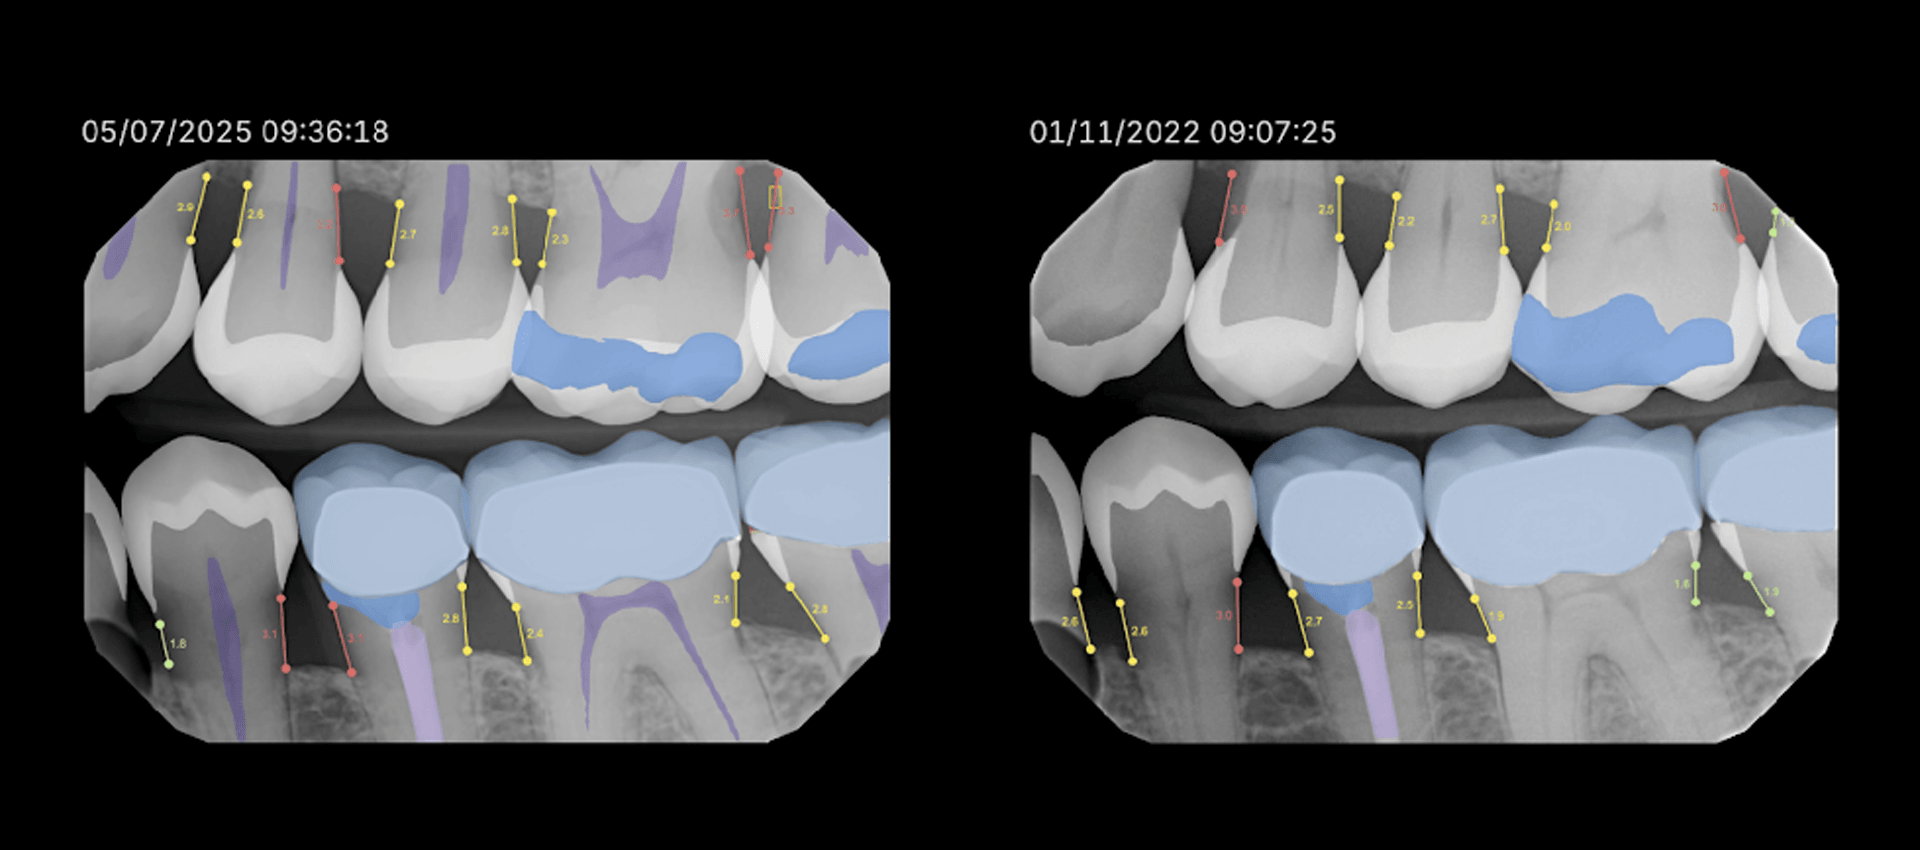

One of my longtime patients has had routine bitewing radiographs taken nearly every year. The last four years of these radiographs were analyzed through Overjet’s AI platform. When I compared one year to the next, everything appeared stable. But when I compared the first and fourth year side by side, a new story emerged. With the help of AI, I discovered she had lost about 0.5 to 0.8 millimeters of bone height. That may sound minimal, but in the world of periodontics, it signals an active process that warrants attention.

AI fills that gap. By measuring bone levels from consistent anatomical landmarks like the cementoenamel junction, AI provides precise, reproducible data that allows clinicians to track small changes with confidence. What might look “the same” visually can, through measurement, reveal a clear trend.

Modern AI visualization tools such as LENS allow radiographs from different years to be viewed side by side, each displaying its respective bone measurements. This view gives clinicians and patients a clear perspective on how small, nearly invisible changes accumulate over time.

Rather than relying on memory or approximation, AI introduces a layer of objectivity. It helps us see the progression that happens quietly, one fraction of a millimeter at a time, empowering earlier and more targeted intervention.

Perhaps the most powerful outcome of AI is how it transforms patient communication. Instead of saying, “your bone looks a little lower than before,” I can show a patient, “your bone height has decreased by 0.7 millimeters over the last four years.”